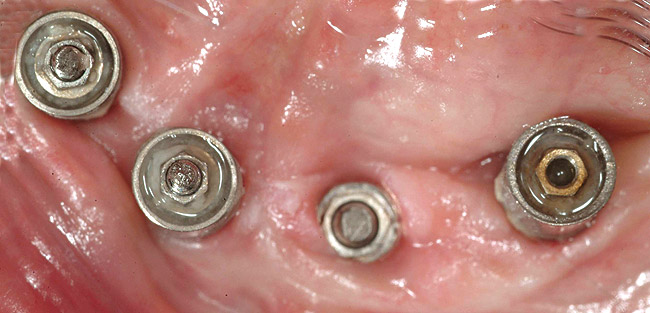

Figure 3  Occlusal view of four anterior mandibular implants. Two of the retaining screws fractured and remained inside the corresponding abutment screws (left). The abutment screw in the left anterior implant fractured, with the apical portion of the screw remaining inside the implant (center).

Figure 3